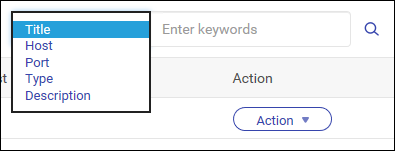

在 MediQPACS 的“AE Management”(AE 管理)屏幕中,用户可以在本地或外部网络上添加、编辑、删除、搜索和测试其他 AE 的连接。

搜索 AE